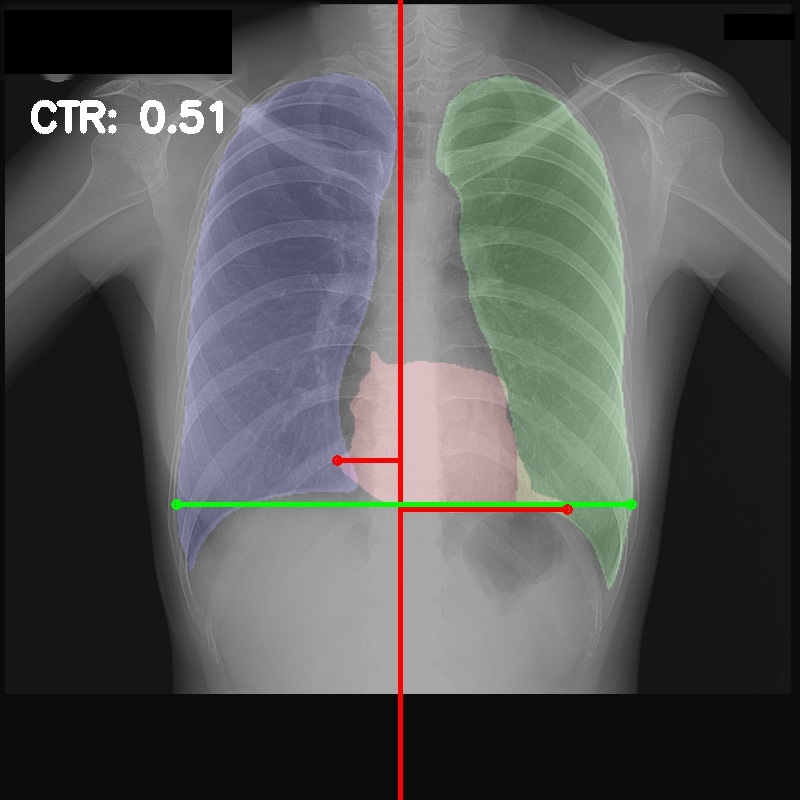

Chest radiography is the most common tool for detecting cardiomegaly due to the low cost and high availability of devices to obtain chest X-ray images. From chest X-ray images, radiologists employ CTR as one of the most important indicators of cardiomegaly due to the simplicity of the calculation. CTR of a chest X-ray image is calculated as cardiac diameter (the diameter of the heart) divided by the thoracic diameter (the diameter of the chest). Specifically, CTR can be calculated from three measurements, , the midline-to-right heart diameter, , the midline-to-left heart diameter, and , the internal diameter of chest [2, 3], as

| (1) |

where and is measured from the greatest perpendicular diameter from midline to right and left heart border, respectively. Figure 1 visualizes the details of CTR calculation. A CTR value of is generally considered to indicate the upper limit of normal.

3.5 Cardiothoracic Ratio Calculation

After obtaining the masks, we calculate CTR with equation 1. We calculate cardiac diameter, , by finding the extreme points on the x-axis of the heart mask and calculate their x-axis distance. Thoracic diameter, , is calculated from extreme points from the lung mask. Figure 4 demonstrates the calculation of each component.

After obtaining heart and lung segments, we calculated , , and and marked them on the image along with CTR value calculated from Equation 1.

Figure 6 shows examples of our CTR calculation, where CTR values along with their , and measurement points are correctly identified. In this image, cardiomegaly is correctly detected by CTR value of .